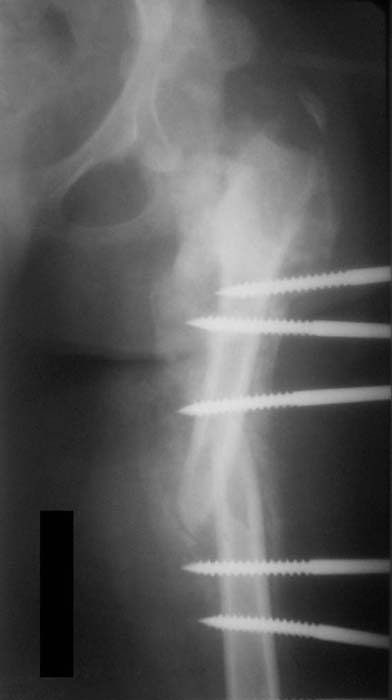

Хотелось бы увидеть рану с разных ракурсов и рентгенограммы таза и бедра. Тогда можно создать представление о площади и глубине раны.

Такая мысль тоже приходила. Не решились, так как:1.Выраженный остеопороз костей таза и бедра, больная тучная - высок риск того, что стержни не выдержат. 2.Сейчас больная передвигается в инвалидном кресле - хоть какая-никакая, а динамизация. Если лишить её этой возможности - застойная пневмония со всеми вытекающими...